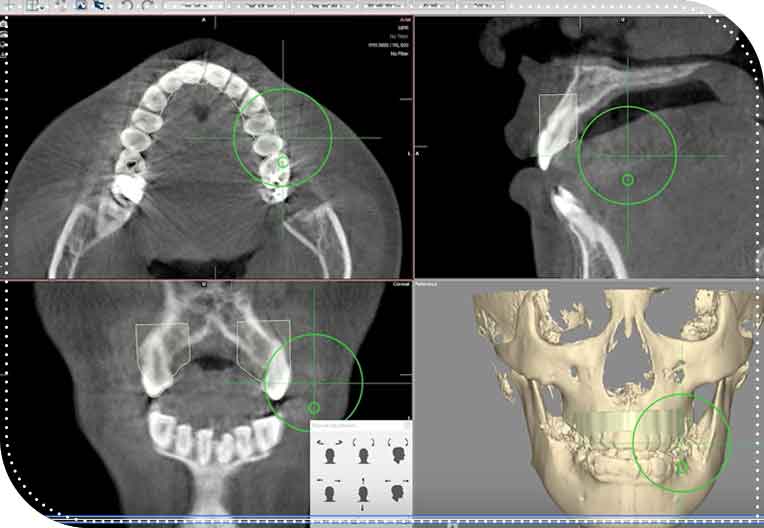

現在はクリンチェック(歯並びの設計ソフト)と歯科用CTをパソコン上でマッチングさせることで以前よりも、より予測実現性の高い治療計画を立てることができるようになりました。

現在はクリンチェック(歯並びの設計ソフト)と歯科用CTをパソコン上でマッチングさせることで以前よりも、より予測実現性の高い治療計画を立てることができるようになりました。